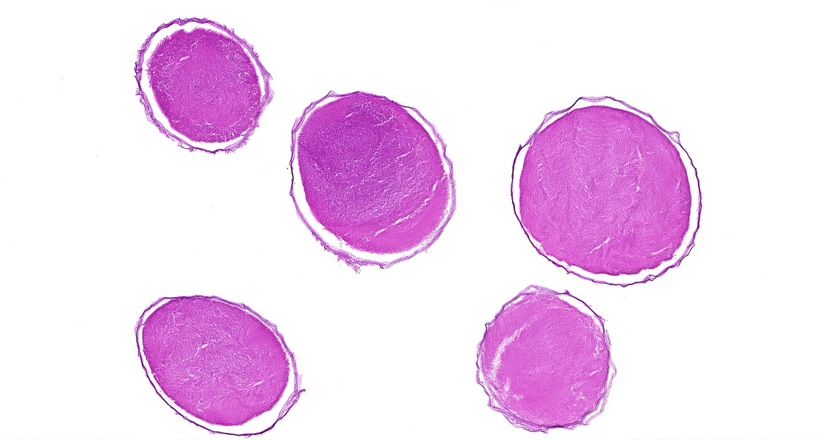

【技術(shù)原理】

蘇木精-伊紅染色法簡稱HE染色法,是最常用的染色方法。蘇木精(hematoxylin)是陽離子染料,能夠?qū)⒓毎藘?nèi)的嗜堿性物質(zhì)染成藍紫色。伊紅(eosin)是陰離子染料,能夠?qū)⒓毎|(zhì)和膠原纖維等染成粉紅色。

案例展示